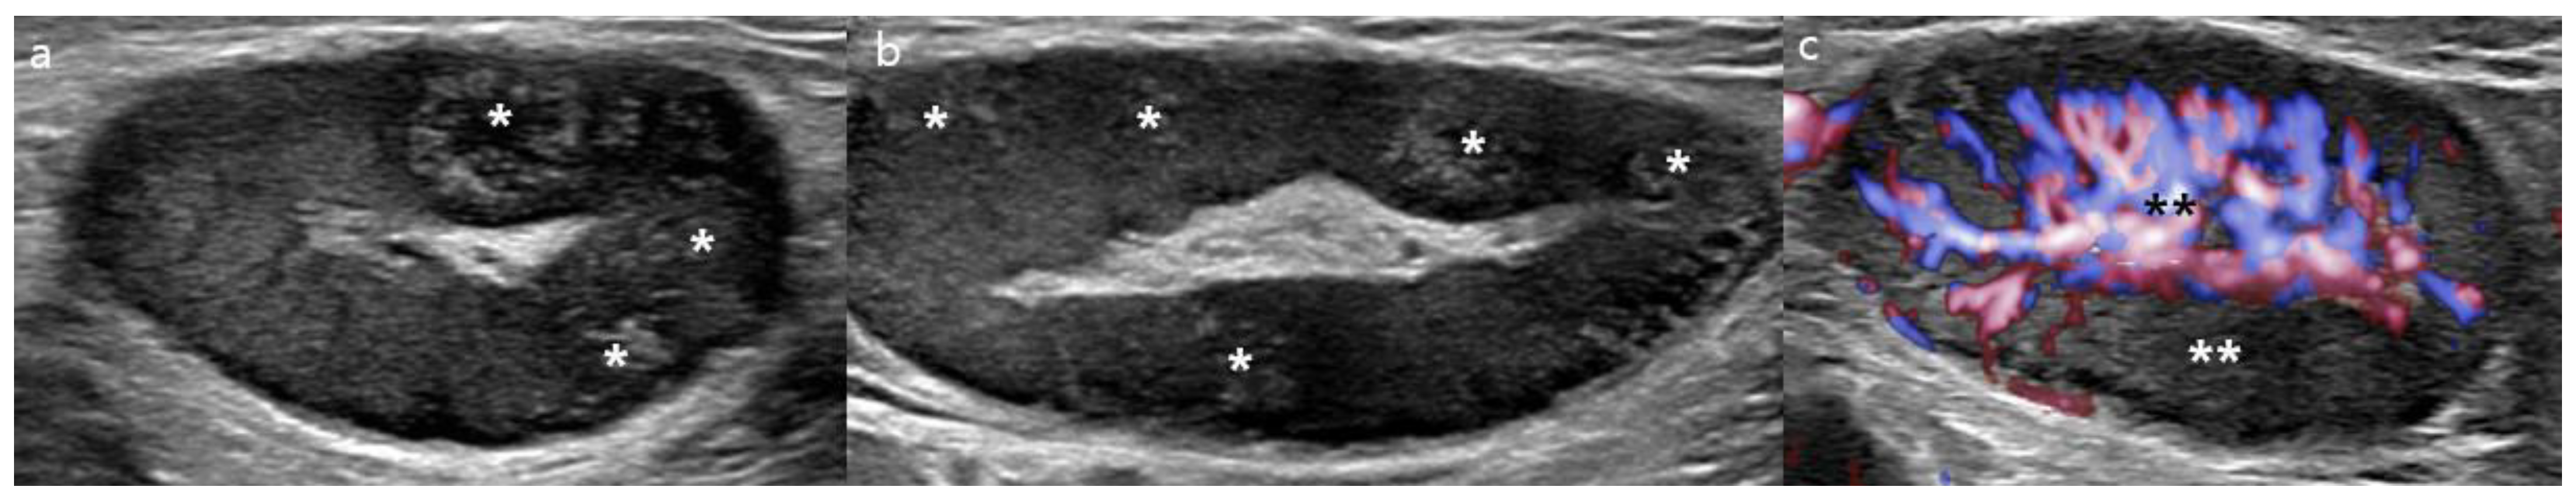

2. Case Report